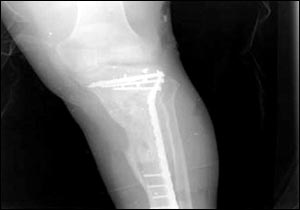

烏代傷腿的X光照片

7月24日,美國國防部通過由美國資助的伊拉克電視臺、兩家阿拉伯衛(wèi)星電視臺以及美國本土的CNN(有線新聞網(wǎng)絡(luò))將薩達(dá)姆的兩個兒子烏代和庫賽遭美軍擊斃慘死的照片公諸于世,同時被曝光的還有1996年烏代遇刺后所拍的傷腿的X光片。據(jù)悉,近60的伊拉克人收看這檔節(jié)目。此前,美軍中央司令部的里卡多·桑切斯中將在巴格達(dá)舉行新聞發(fā)布會時說,判斷烏代和庫賽被打死的依據(jù)是在現(xiàn)場發(fā)現(xiàn)的牙齒以及曾任薩達(dá)姆助手的目擊證人的指認(rèn)。